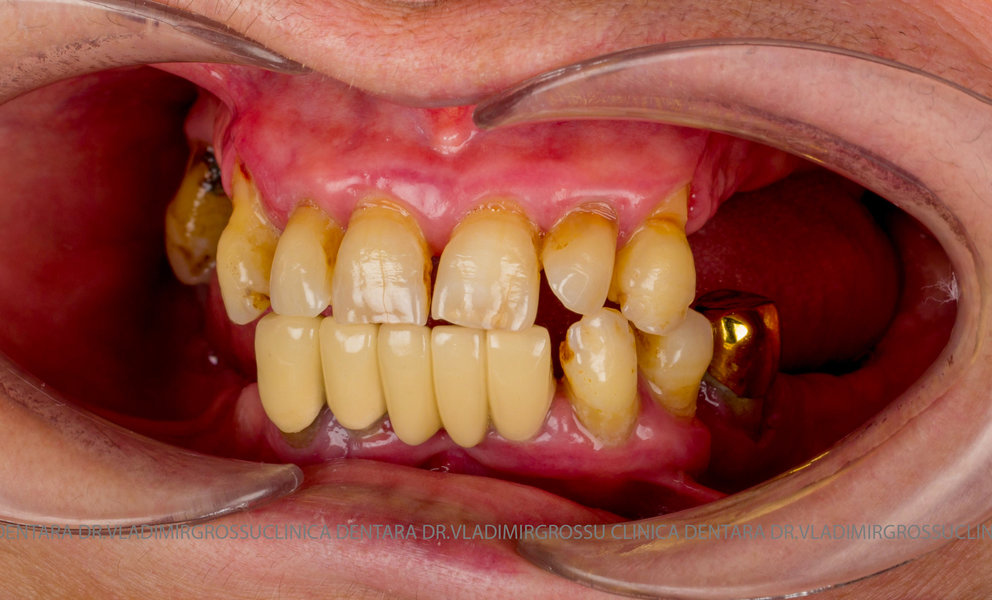

Cazuri clinice conceptul All-on-6

Caz 1